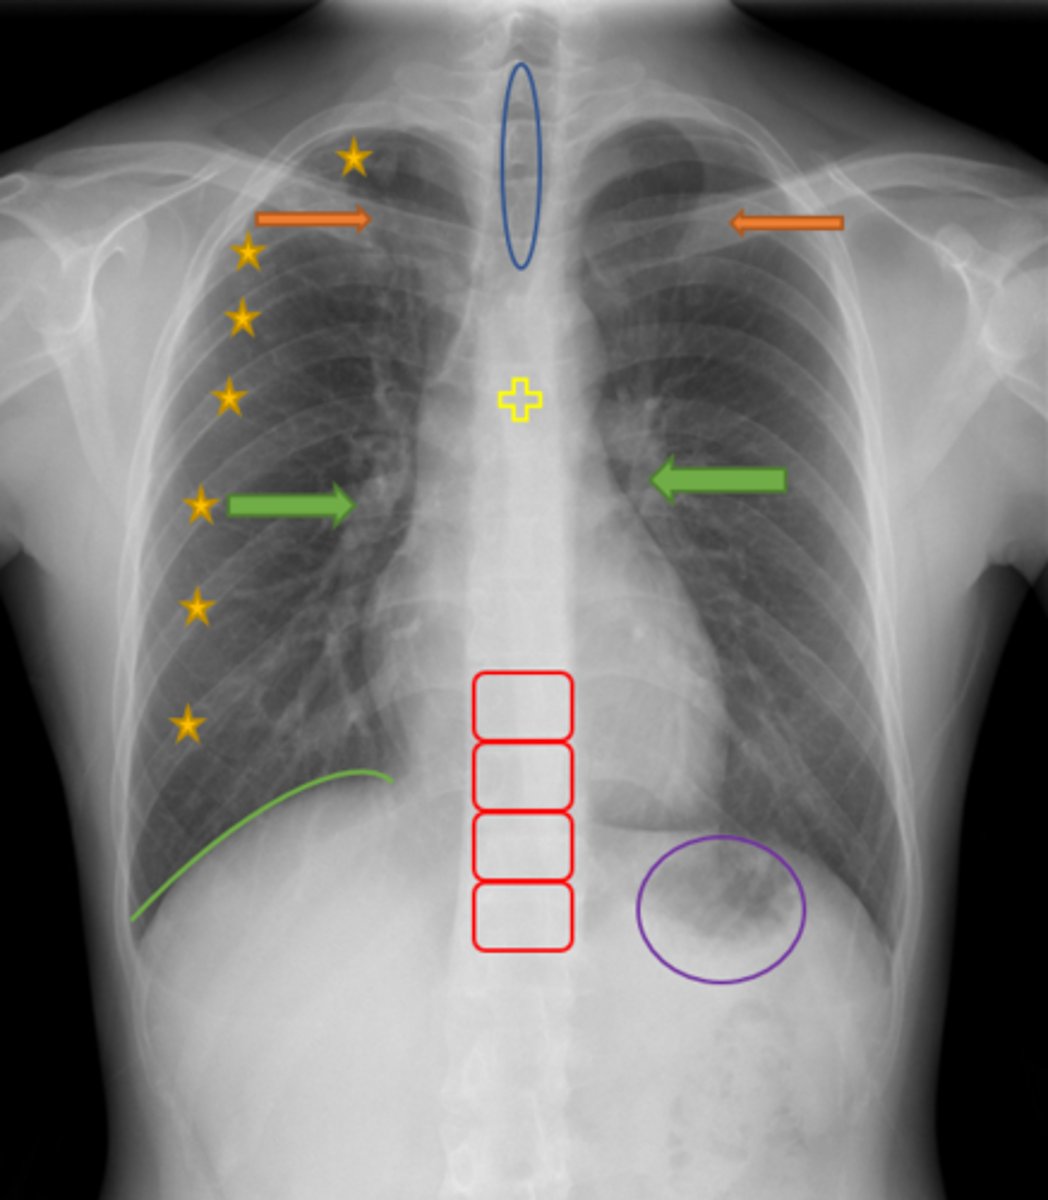

Trachea

Blue Oval

Pulmonary arteries

Green Arrows

Vertebrae/spine

Red Blocks

Clavicle

Orange Arrows

Ribs

Yellow Stars

Diaphragm

Green Line

Gastric bubble/stomach

Purple Circle

Carina

Yellow Cross